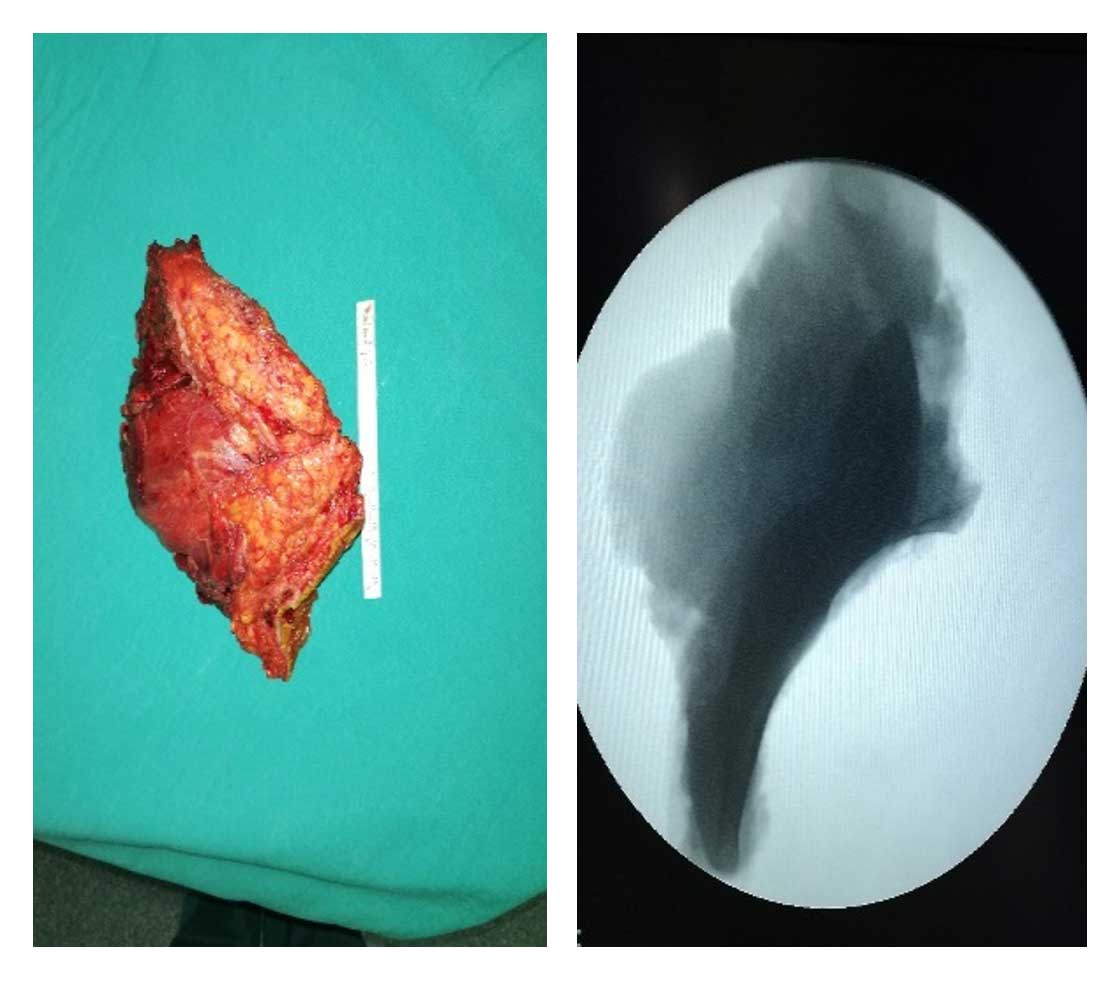

Ameliyat Esnası: Çıkarılan rezeksiyon dokusunun klinik ve radyolojik görüntüsü.